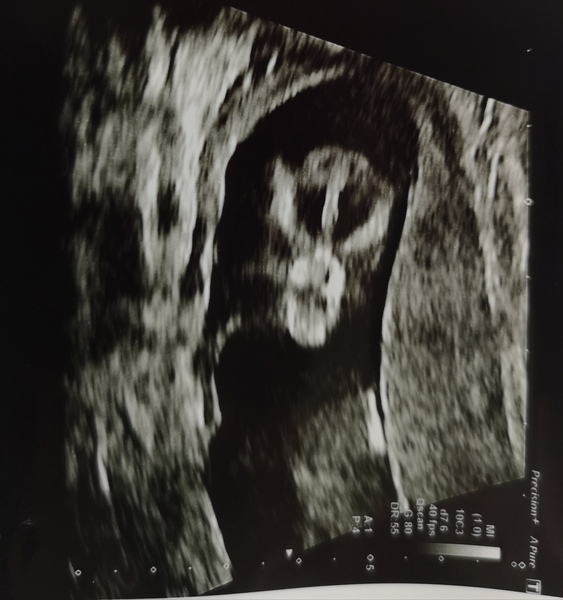

Scan done. Took quite a while as beany kept facing us and rolling around. My dates got moved from 12/3 to 13/1! What, crazy. I'm so chuffed to have pics though.

I had my scan yesterday and measuring at least 4 days ahead and the sonographer was pretty sure it was a boy! I'll wait until the 20 week scan before I buy anything blue though ha!

Had ours today too 11+1 which is around what I thought and all looks good. Back in 2 weeks for the nuchal measurement and blood test so excited to see baby again.